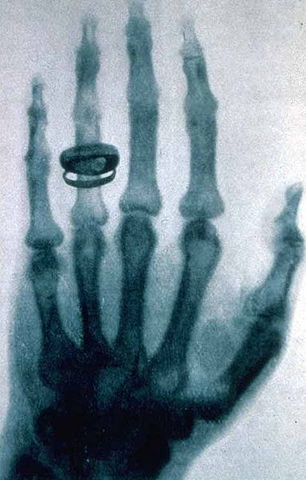

• Descubrimiento de los Rayos X

Descubrimiento de los Rayos X

Descubiertos por Wilhelm Conrad Roetgen. La denominación rayos X designa a una radiación electromagnética, invisible, capaz de atravesar cuerpos opacos y de imprimir las películas fotográficas.